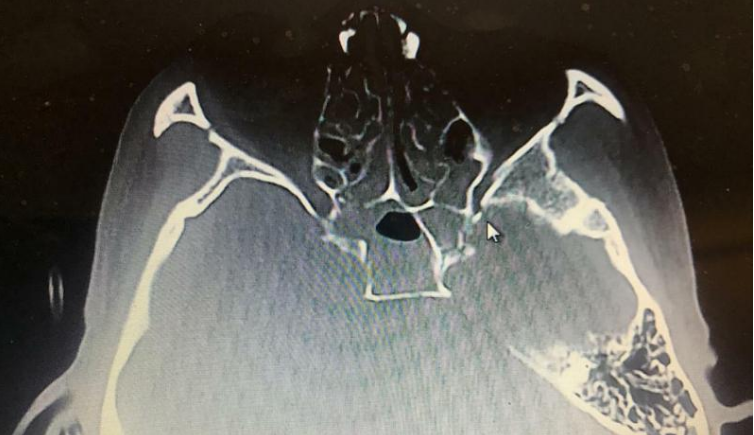

靠卖菜维生的28岁小伙子因三轮车侧翻头破血流,失去意识。醒后发现左眼完全看不见了!经专家紧急手术,近日重见光明,左眼视力基本恢复正常,看报纸和手机都已完全没有问题。